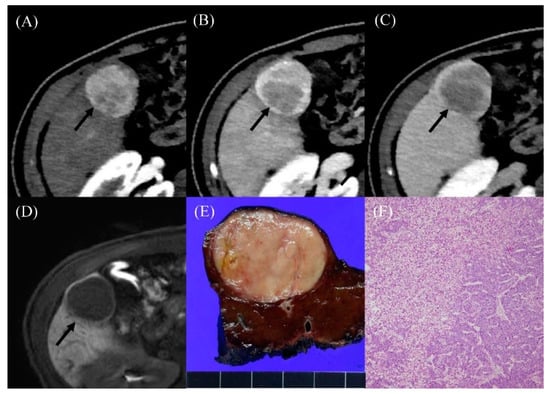

| Largest APHE nodule diameter (cm) | 4.0 (2.3–4.4) | 1.7 (1.2–2.1) | 0.03 |

| Washout on PVP | 0.006 | ||

| No or unknown | 2 (28.6%) | 11 (100.0%) | |

| Yes | 5 (71.4%) | 0 (0.0%) | |

| AFP (ng/mL) | 160.6 (90.6–483.7) | 2.9 (2.3–3.5) | <0.001 |